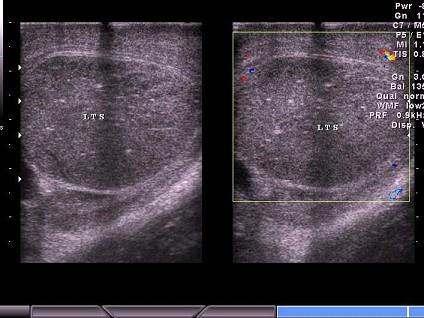

问题 男性,于晨前起床时阴囊急剧疼痛,超声见睾丸肿大,CDFI:血流信号消失。如图所示,考虑为?(?)

选项 A.附睾炎 B.睾丸炎 C.睾丸扭转 D.睾丸肿瘤 E.睾丸结核

答案 C